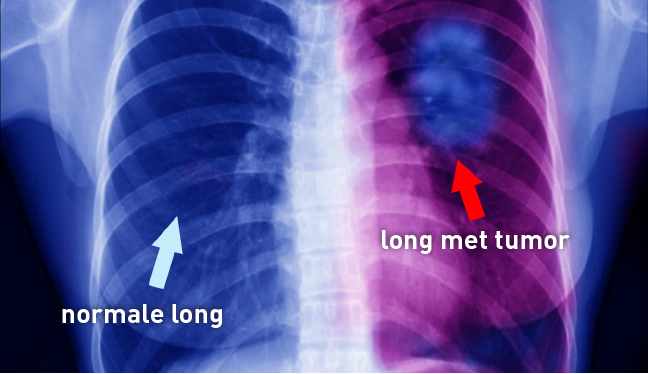

Volledige weergave van afbeelding: 168 KB | View image Bekijken Afbeelding downloaden Download